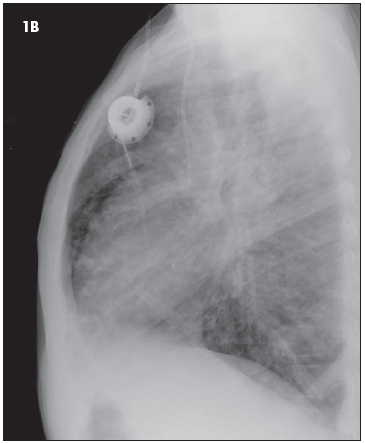

1. The chest radiographs (Figure 1) of a 9-year-old child reflect the classic findings of a particular disease. Among other findings, the size of the patient's heart is_____?

1. The chest radiographs (see Figure 1) of a 9-year-old child reflect the classic radiographic appearance of CF. Among other findings, the size of the patient's heart is small to normal. (B is the correct choice.)

The patient's heart is probably of normal size, but the hyperexpansion commonly seen in patients with CF may make it seem relatively small. This phenomenon is frequently observed in older patients with emphysematous lungs. A small cardiac silhouette may also be seen in patients with asthma. The finding of microcardia could also suggest a hypovolemic state in other patients.

Other common radiographic and cross-sectional imaging (CT) findings of CF include focal atelectasis with or without hyperaeration, bronchiectasis seen as dilated tubular tracts or end-on with a cystic appearance, parahilar streaky opacities, peribronchial thickening, and mucous plugging.

3. Is there evidence of hyperinflation? The answer is yes. (A is correct.)

If the frontal view isn't enough to persuade you (count the 10 to 11 posterior ribs on the frontal view), take a look at the lateral view. The diaphragms are nearly completely flattened and there is a barrel shape appearance to the chest that results from anterior expansion (the anterior clear space) and bowing.

The radiograph shown here (see Figure 1) was interpreted without the benefit of earlier films at our institution. Thus, the presence of acute findings cannot be determined. (C is the correct choice.) Although no acute findings are suspected, a more confident interpretation would be possible if earlier films had been submitted for comparison.